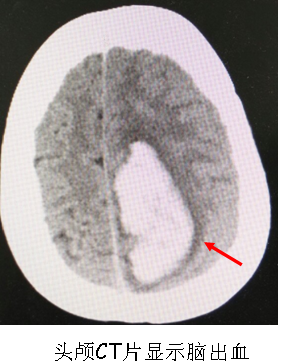

9月8日下午,我院DSA手术室正在紧张地为二名脑出血患者行全脑血管造影手术,无影灯下手术医生与护士配合默契,“加压滴注、排气、穿刺动脉、置导管鞘、推造影剂、减影……”一系列手术操作有条不紊地进行着。

患者王某,女性,54岁,因左侧顶枕叶脑出血收住入院,既往无高血压病史,病情稳定后经DSA检查现已明确为左侧顶叶脑动脉静脉畸形;另一患者肖某,女性,74岁,因自发性蛛网膜下腔出血收住入院,经本次手术检查已明确为右侧大脑后动脉动脉瘤。两名患者通过本次手术均很快找到出血病因,为后续治疗指明方向及制定治疗方案提供了可靠依据。